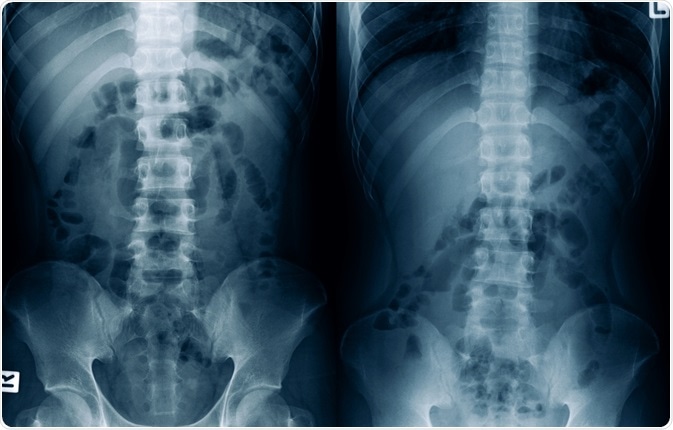

Ileus is a term used to describe the functional and non-mechanical inhibition of propulsive bowel activity, regardless of the pathologic mechanism. Ileus should be differentiated from a mechanical bowel obstruction, which is when GI motility is inhibited due to different structural abnormalities like tumors, hernias, intestinal adhesions, and twisting of the intestine.

A distinction between postoperative ileus and mechanical small-bowel obstruction is sometimes difficult and confusing. A useful tool for distinguishing these two entities is computerized tomography (CT), although even plain radiography can help establish a correct diagnosis in certain cases.